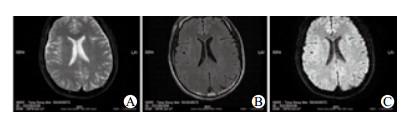

1 资料与方法患者, 男, 40岁, 喷洒高效氯氟氰菊酯4 d后出现张口、伸舌困难, 言语不能就诊我院, 查体:体温正常, 双眼睑、球结膜充血水肿, 颈亢, 四肢肌张力高, 腱反射亢进, 克布氏征及病理征阴性, 双手背侧可见皮肤散在皮损, 疑诊高效氯氟氰菊酯中毒, 予以补液、利尿等处理后症状无缓解, 进一步出现吞咽困难, 角弓反张, 行走困难, 声音刺激及接触患者时症状加重。既往否认癫痫等慢性疾病史, 两年前曾被铁钉扎伤, 未肌注破伤风抗毒素。实验室检查:胆碱酯酶8 580.3 U/L。血液及尿液毒物检测均未检出常见药物、杀虫剂及毒鼠强成分。颅脑MRI未见异常(图 1)。脑电图未见明显异常改变, 视频脑电地形图未见明显异常分布。肌电图未见神经源性及肌源性改变。入院后患者出现频繁发作性抽搐, 予以气管插管, 同时予以大剂量安定持续泵入止痉、丙泊酚镇静, 患者痫性发作仍未见明显改善, 在充分镇静下给予维库溴铵肌松后缓解。24 h停用肌松药物后仍有频繁抽搐(20~30次/d), 给予巴氯芬、丙戊酸钠、氯硝西泮联合治疗, 20 d后发作次数逐渐减少, 肌张力逐渐恢复正常, 1个月后完全恢复正常, 出院后随访未再有痫样发作。

| A:MRI T2WI脑内未见明显异常信号,侧脑室不大,脑沟裂不宽,中线结构居中; B:MRI FLAIR脑内未见明显异常信号; C:MRI DWI脑内未见异常高信号 图 1 颅脑MRI平扫 |